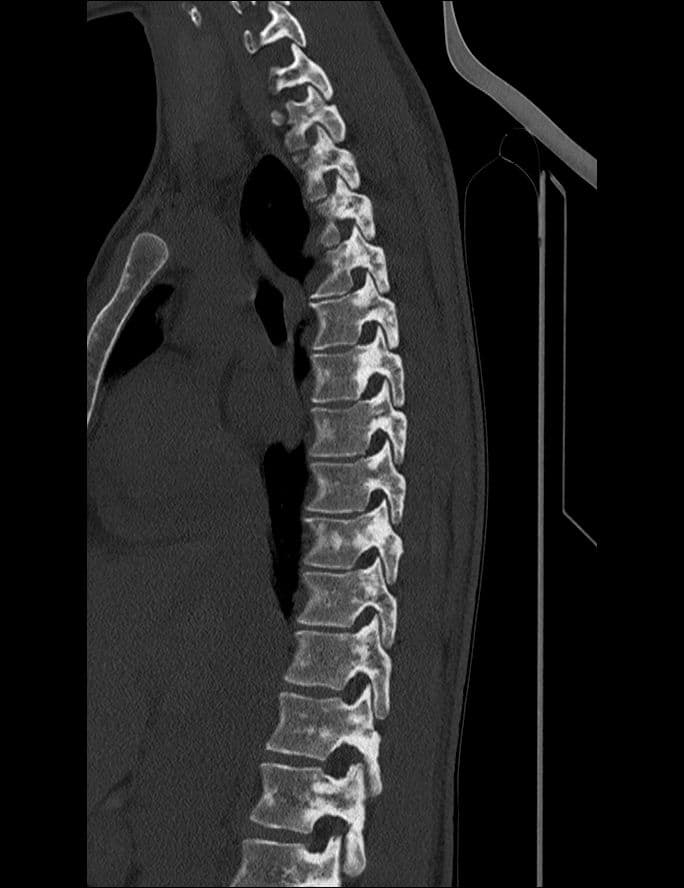

Attente osseuse axiale de la sclérose tubéreuse de Bourneville, ou complexe de sclérose tubéreuse (TSC).

CTMRI

Tumeur bénigne relativement rare de découverte fortuite sur un bilan de lombalgie.